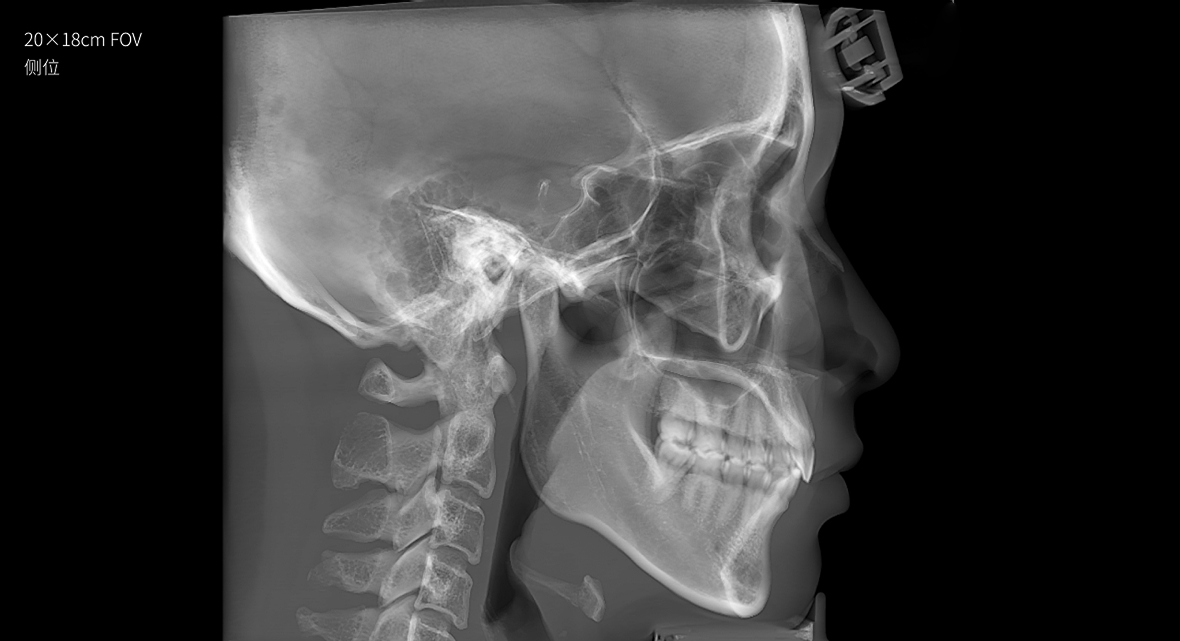

只需一次单圈扫描即可获得CT、3D全景和3D正/侧位影像,并能同时生成3D TMJ视图

提高诊疗效率,避免过度检查,减少患者所受的辐射

• 3D 正侧位

3D 正侧位